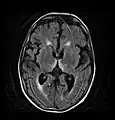

Axial MRI FLAIR image showing hyperintense signal in the mesial dorsal thalami, a common finding in Wernicke encephalopathy. This patient was nearly in coma when IV thiamine was started, he responded moderately well but was left with some Korsakoff type deficits.

Axial MRI FLAIR image showing hyperintense signal in the mesial dorsal thalami, a common finding in Wernicke encephalopathy. This patient was nearly in coma when IV thiamine was started, he responded moderately well but was left with some Korsakoff type deficits. Axial MRI B=1000 DWI image showing hyperintense signal indicative of restricted diffusion in the mesial dorsal thalami

Axial MRI B=1000 DWI image showing hyperintense signal indicative of restricted diffusion in the mesial dorsal thalami Axial MRI FLAIR image showing hyperintense signal in the periaqueductal gray matter and tectum of the dorsal midbrain

Axial MRI FLAIR image showing hyperintense signal in the periaqueductal gray matter and tectum of the dorsal midbrain